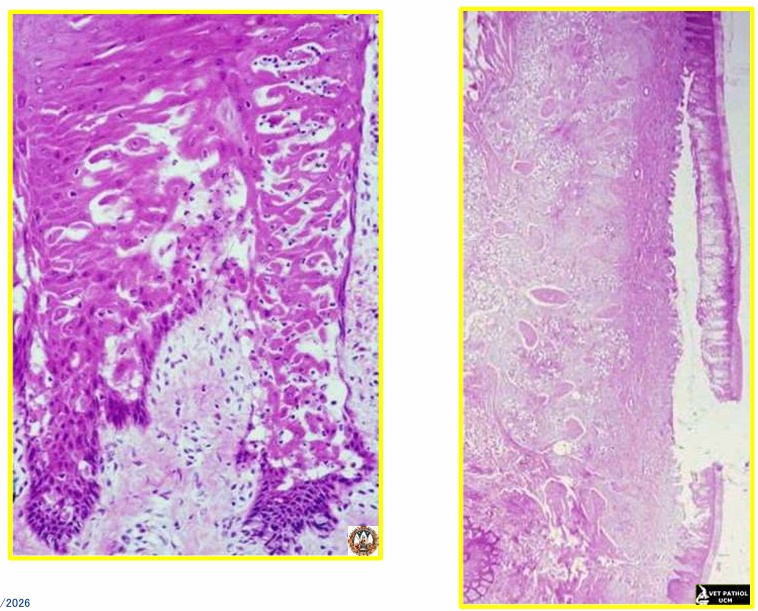

DIARREA VÍRICA BOVINA (PESTEVIRUS) → lesiones en todo aparato digestivo

gingivitis y glositis

FIEBRE CATARRAL MALIGNA (HV)

LENGUA AZUL (ORBOVIRUS)

descarga nasal, edema y hemorragias en lengua

micronecrosis fibras musculares estriadas